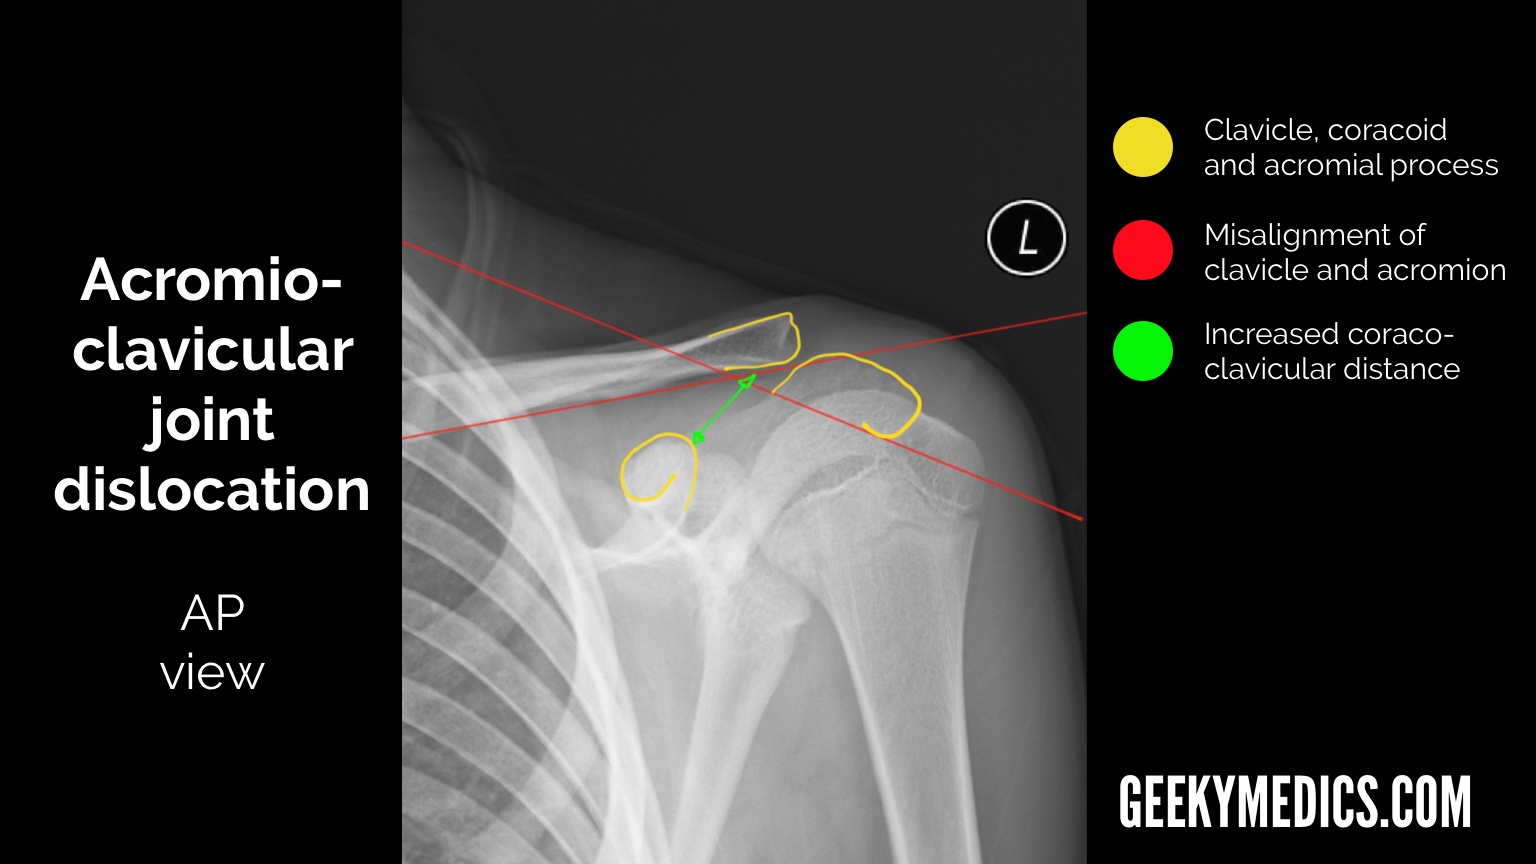

From geekymedics.com

Shoulder Xray Interpretation Radiology Geeky Medics Subluxation Of Shoulder X Ray The shoulder can dislocate posteriorly, but. A partial dislocation is also called a subluxation. A health care provider inspects the affected area for tenderness, swelling or deformity and checks for signs of nerve or blood vessel. Describe the diagnostic approach for evaluating shoulder subluxation injuries. Following a seizure, the shoulder often. Shoulder dislocation is a term often used loosely to. Subluxation Of Shoulder X Ray.

Shoulder Xray Interpretation Radiology Geeky Medics Subluxation Of Shoulder X Ray Shoulder dislocation is a term often used loosely to indicate dislocation of the head of the humerus from the glenoid of the scapula. A health care provider inspects the affected area for tenderness, swelling or deformity and checks for signs of nerve or blood vessel. The shoulder can dislocate posteriorly, but. Describe the diagnostic approach for evaluating shoulder subluxation injuries.. Subluxation Of Shoulder X Ray.

Shoulder Xray Interpretation Radiology Geeky Medics Subluxation Of Shoulder X Ray A partial dislocation is also called a subluxation. Shoulder dislocation is a term often used loosely to indicate dislocation of the head of the humerus from the glenoid of the scapula. A health care provider inspects the affected area for tenderness, swelling or deformity and checks for signs of nerve or blood vessel. Following a seizure, the shoulder often. The. Subluxation Of Shoulder X Ray.

Shoulder Xray Interpretation Radiology Geeky Medics Subluxation Of Shoulder X Ray A partial dislocation is also called a subluxation. Following a seizure, the shoulder often. Describe the diagnostic approach for evaluating shoulder subluxation injuries. The shoulder can dislocate posteriorly, but. A health care provider inspects the affected area for tenderness, swelling or deformity and checks for signs of nerve or blood vessel. Shoulder dislocation is a term often used loosely to. Subluxation Of Shoulder X Ray.

Shoulder Xray Interpretation Radiology Geeky Medics Subluxation Of Shoulder X Ray Shoulder dislocation is a term often used loosely to indicate dislocation of the head of the humerus from the glenoid of the scapula. The shoulder can dislocate posteriorly, but. Describe the diagnostic approach for evaluating shoulder subluxation injuries. A partial dislocation is also called a subluxation. A health care provider inspects the affected area for tenderness, swelling or deformity and. Subluxation Of Shoulder X Ray.

Shoulder Xray Interpretation Radiology Geeky Medics Subluxation Of Shoulder X Ray Following a seizure, the shoulder often. Other potential causes of a shoulder dislocation include seizures and electrocutions. Shoulder dislocation is a term often used loosely to indicate dislocation of the head of the humerus from the glenoid of the scapula. The shoulder can dislocate posteriorly, but. A partial dislocation is also called a subluxation. A health care provider inspects the. Subluxation Of Shoulder X Ray.